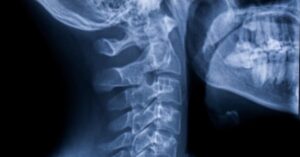

Beyond the Back: Surprising Causes of Sciatica Not Found in the Lumbar Spine

When you feel that unmistakable lightning bolt of pain searing from your glutes down to your toes, the first suspect is almost always a herniated disc. While lumbar spine issues account for roughly 90% of sciatica cases, the remaining 10% present a diagnostic puzzle. If your MRI shows a perfectly healthy lower back but your leg is still screaming, it’s time to look at extraspinal causes—the “sciatica mimics” that originate outside the vertebral column.